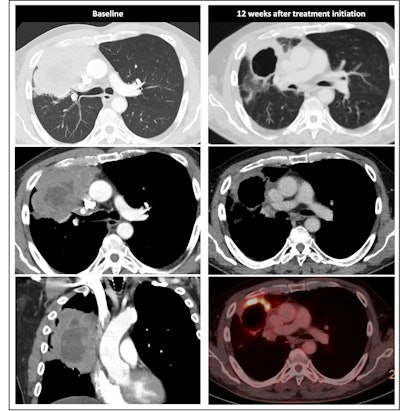

Radiological response inconsistent with pathological response: 69-year-old patient with non-small cell lung cancer (NSCLC) received a neoadjuvant treatment with three cycles of immune-checkpoint inhibitor therapy plus chemotherapy (ICIT + C, carboplatin/pemetrexed/pembrolizumab). 12 weeks after treatment began, the patient showed complete pathologic response (ypTo, pNo) but only partial radiological response.

The researchers noted in a poster presentation at RSNA in Chicago that a minority of patients with cPR show complete radiological response (24% vs. 1.1%). Also, ICIT leads to inflammatory cell infiltration with edema and later on tumor cell necrosis or fibrosis, the authors continued. Initially, this may lead to no change in lesion size, increase or appearance of new lesions (pseudoprogression), and mimicking of residual disease.

Most patients will have a residual tumor and fibrotic tissue, leading to insufficient assessment with standard-of-care imaging, while major pathologic response involves a reduction in tumor size with residual tissue and no major pathologic response means a reduction in tumor size or stable disease.

Radiological response inconsistent with pathological response: 75-year-old patient received a neoadjuvant treatment with three cycles of ICIT + C (carboplatin/pemetrexed/pembrolizumab). 12 weeks after treatment began, the patient showed complete pathologic response (ypTo, pNo) but only partial radiological response.